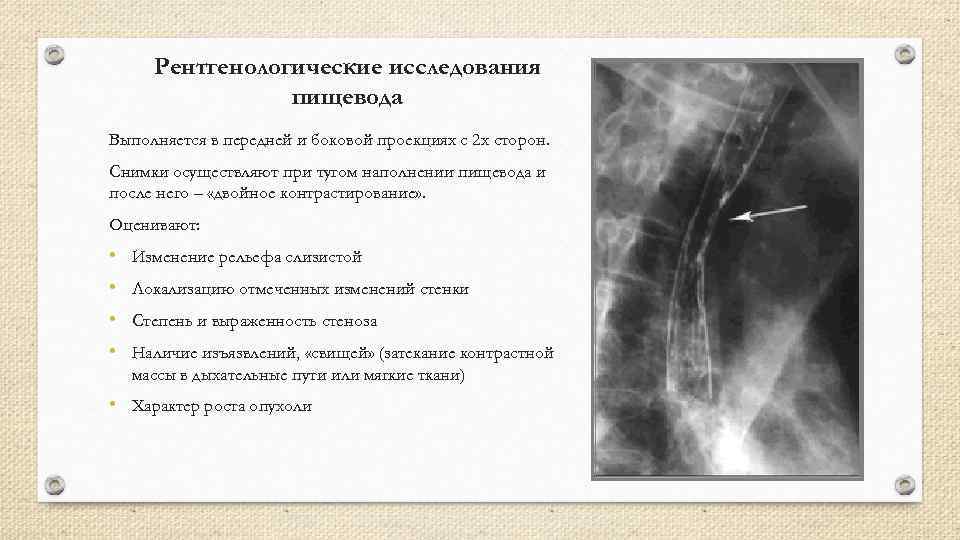

Рентгенологические исследования пищевода Выполняется в передней и боковой проекциях с 2 х сторон. Снимки осуществляют при тугом наполнении пищевода и после него – «двойное контрастирование» . Оценивают: • Изменение рельефа слизистой • Локализацию отмеченных изменений стенки • Степень и выраженность стеноза • Наличие изъязвлений, «свищей» (затекание контрастной массы в дыхательные пути или мягкие ткани) • Характер роста опухоли

Рентгенологические исследования пищевода Выполняется в передней и боковой проекциях с 2 х сторон. Снимки осуществляют при тугом наполнении пищевода и после него – «двойное контрастирование» . Оценивают: • Изменение рельефа слизистой • Локализацию отмеченных изменений стенки • Степень и выраженность стеноза • Наличие изъязвлений, «свищей» (затекание контрастной массы в дыхательные пути или мягкие ткани) • Характер роста опухоли